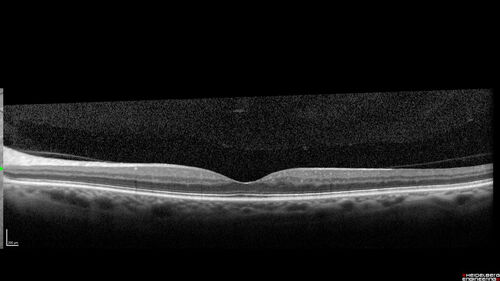

| Album name: | scohen125 / Hairy Cell Leukemia - Hemorrhage and twig BRVO |